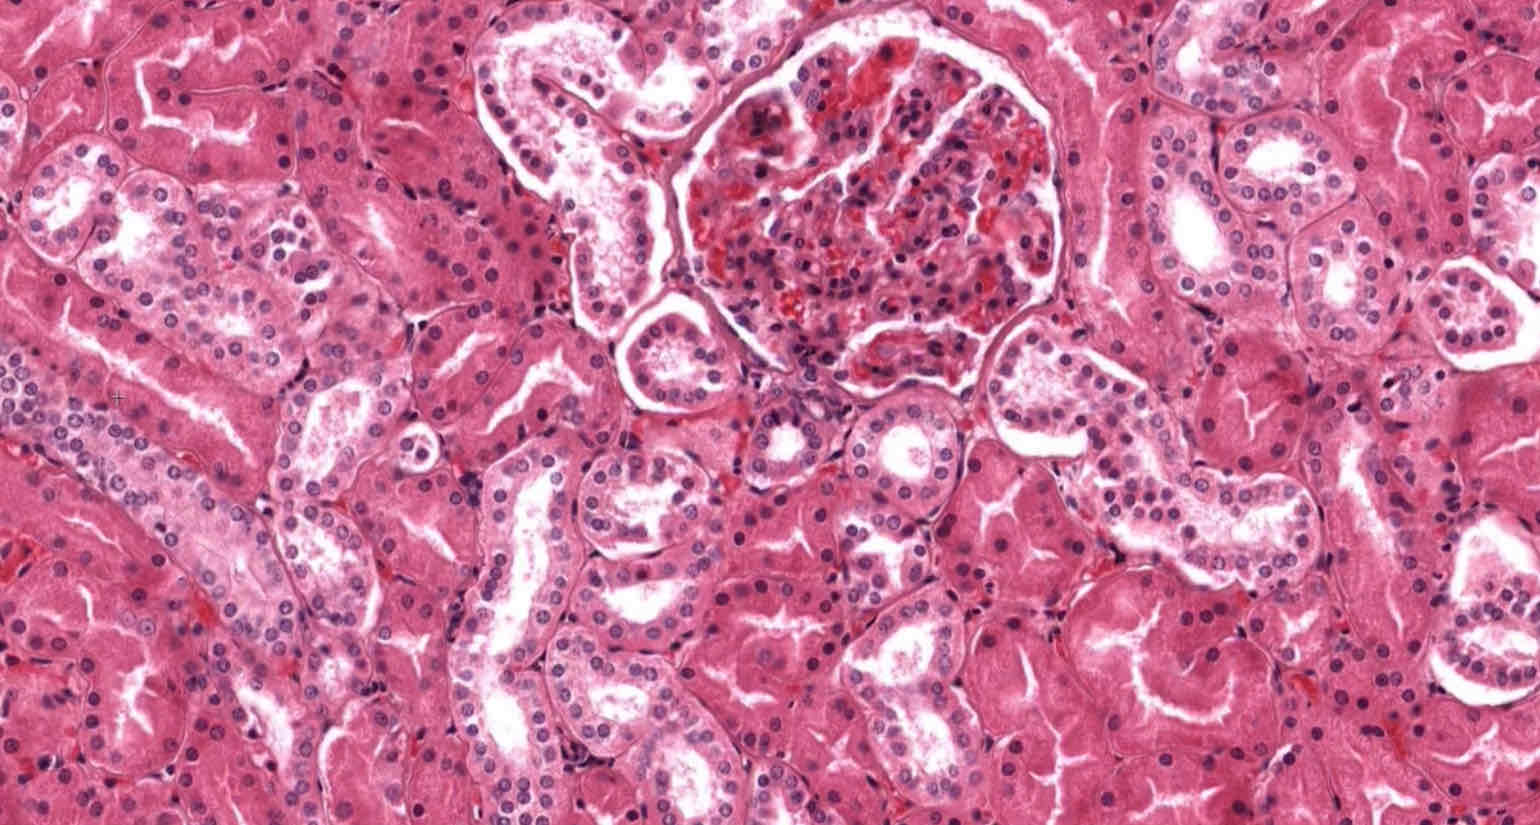

Simple cuboidal epithelium

Location of simple cuboidal epithelium

Gland ducts

Function of simple cuboidal epithelium

Absorption, secretion